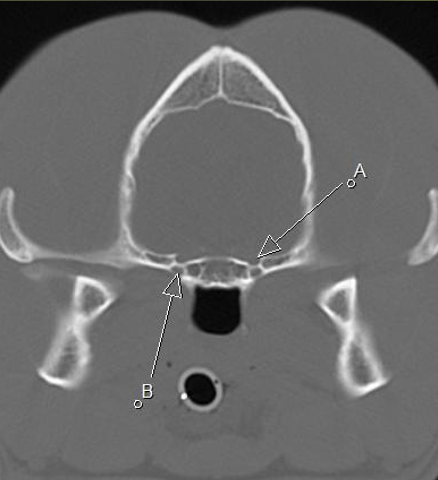

A orbital fissure

B rostral alar foramen leading to alar canal, round foramen inside the skull